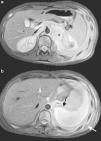

Presentamos el caso de una adolescente de 15 años de edad, sin antecedentes de interés, que presenta dolor dorsolumbar progresivo y astenia de 20 días de evolución. Dicho dolor genera disnea de pequeños-moderados esfuerzos. En la auscultación pulmonar se observa hipoventilación marcada en el hemitórax izquierdo. Se realiza radiografía de tórax (fig. 1) que evidencia derrame pleural masivo izquierdo, procediéndose a toracocentesis evacuadora sin dejar tubo de drenaje. Se evacúan 1.500ml de líquido pleural de coloración amarillenta (pH: 7,41 con predominio de linfocitos, glucosa: 82mg/dL, proteínas: 4,3g/dL, LDH: 391U/L y ADA: 26,3U/L). Evoluciona desfavorablemente, con aumento de la dificultad respiratoria y reacumulación de líquido en la cavidad pleural. Se realiza nueva toracocentesis, manteniéndose el drenaje con aspiración durante 5 días. Se obtienen aproximadamente 5 L de líquido con características de exudado. El despistaje microbiológico es negativo. En la resonancia magnética abdominal (fig. 2) se visualiza una masa retroperitoneal superior y lesiones focales que afectan a múltiples cuerpos vertebrales y a la cresta ilíaca izquierda, sugestivas de metástasis óseas.